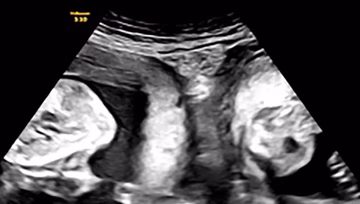

Rijetka pojava zabilježena u Kini: Majka s dvije maternice rodila blizance - po jedno iz svake maternice Svijet | 2. okt. | 0